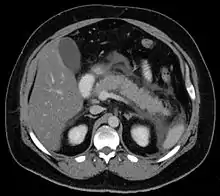

من أكثر أسباب التهاب البنكرياس شيوعاً هي حصوات المرارة وإدمان الكحول. ومن الأسباب الأخرى هي الإصابة المباشرة للبنكرياس جراء الحوادث، بعض الأدوية، أو بعض أنواع العدوى (كالتهاب الغدة النكافية)، أو بعض أنواع الأورام. التهاب البنكرياس المزمن قد يتطور كنتيجة لالتهاب البنكرياس الحاد، وهو غالباً ينتج من شرب الكحول المزمن بكميات كبيرة. ومن الأسباب الأخرى هي ما يلي: ارتفاع نسبة الدهون أو الكالسيوم في الدم، بعض الأدوية، وبعض الأمراض الجينية مثل التليف الكيسي،[2] والتدخين الذي قد يزيد احتمالية الإصابة بالتهاب البنكرياس بنوعيه (المزمن والحاد).[3][4] تشخيص التهاب البنكرياس يعتمد على ارتفاع نسبة أي من الأميلاز أو الليباز (إنزيمات) بنسبة تعادل ثلاثة أضعاف المستوى الطبيعي في الدم. لكن في بعض حالات التهاب البنكرياس المزمن، مستوى هذه الإنزيمات قد يكون ضمن المعدل الطبيعي. التصوير الطبي (بواسطة الأشعة المقطعية أو الموجات فوق الصوتية) هو أيضاً أداة مساندة للتشخيص وقد تكون ذات فائدة.[2]

- دراسة تصويرية مع تغييرات مميزة. أشعة مقطعية، أو أشعة مغناطيسية، أو أشعة صوتية للبطن، أو قد تستخم الأشعة الصوتية بالمنظار للتشخيص.

بخصوص الأشعة التشخيصية، فإن الأشعة فوق الصوتية ملائمة، وسهلة، وليست غالية الثمن.[24] هذه الطريقة أكثر حساسية ودقة لالتهاب البنكرياس بسبب حصوات المرارة من كل طرق التصوير الأخرى.[23] ومع ذلك، فإن منظر البنكرياس في 25-35% من المرضى قد يُحجب من قبل غاز الأمعاء مما يجعل التقييم صعباً.[22]

عادة ما يتم تنفيذ مسح بأشعة مقطعية مُحسنة متباينة بعد مرور أكثر من 48 ساعة من بدء الألم لتقييم موت الأنسجة البنكرياسية، والزيادة في سوائل البنكرياس، بالإضافة إلى التنبؤ بحدة المرض. وقد تكون الأشعة المقطعية المبكرة مُطمئنة بشكل خاطئ.